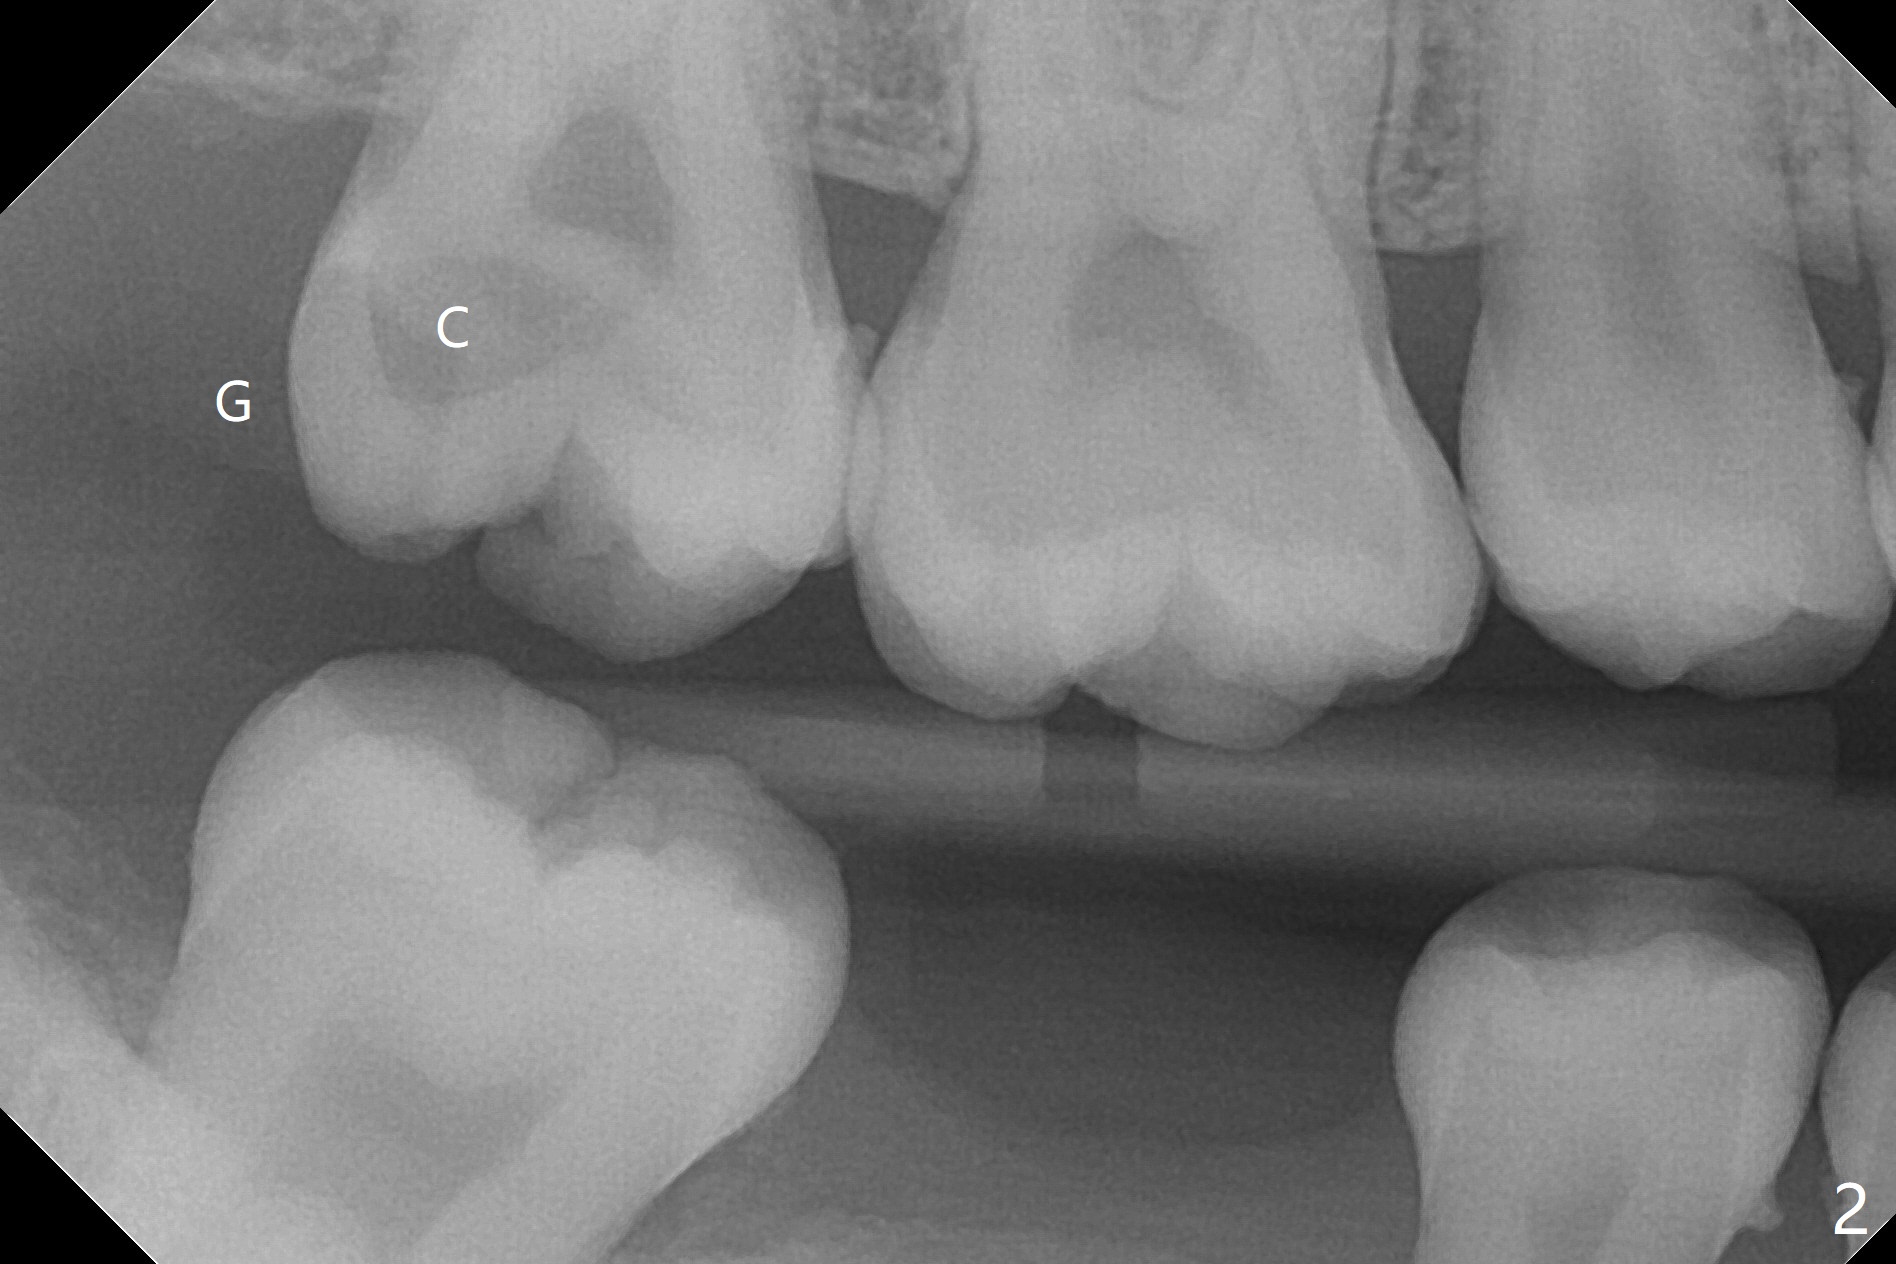

23岁女留学生,即将毕业回国,右上7夜间痛(图一),远中龈下龋,牙龈增生,局部垂直距离小。两三天考虑后,她回来深洗(图二),同意拔除,植骨(皮质,图三),放置GEM Cap,牙周胶水固定,有限垂直距离,肥大颊粘膜,觉得缝合困难。放置间隙保持器必须压到胶原膜,牙周敷料必须放置,防止保持器颊侧臂刺激粘膜。上颌第二磨牙植骨很麻烦,如果使用粘性骨粉,就方便多了。在做深洗时,可以抽血制备PRF,不浪费时间,但愿效果好(信则灵)。